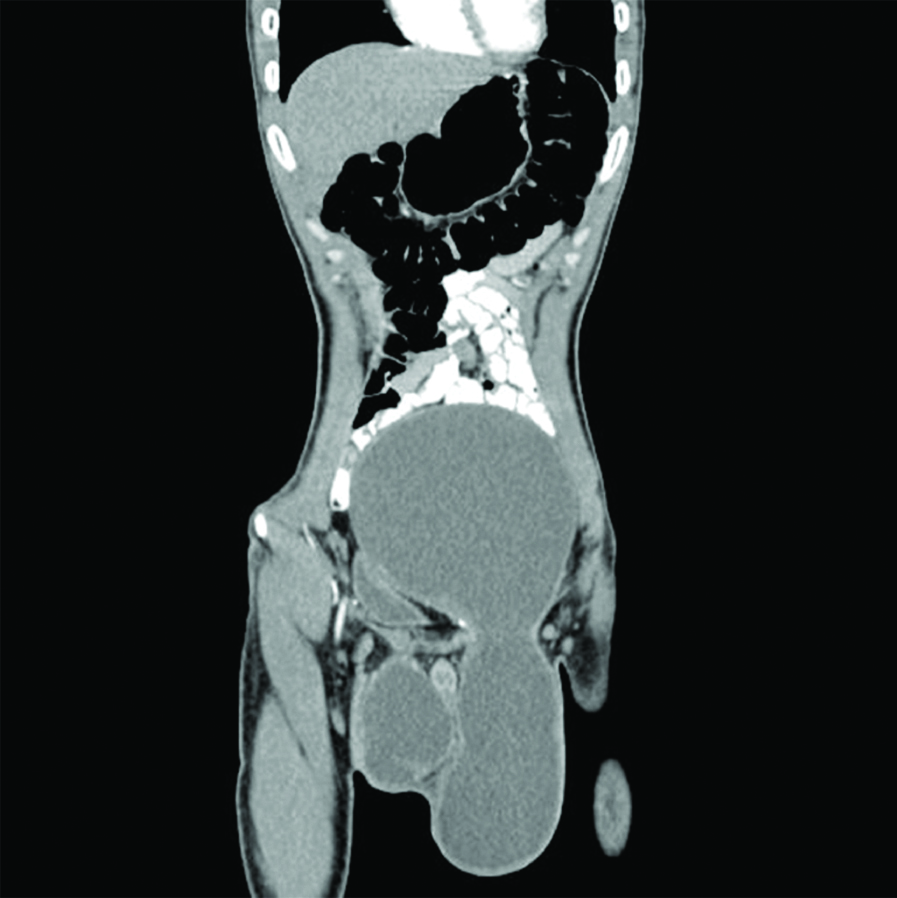

A 27-year-old male presented with bilateral scrotal swelling and gradually progressing abdominal distension since six months, there was no history of trauma, pain or retention of urine. On physical examination, a huge abdominal mass extending from the inguinal crease to costal margin was revealed along with bilateral scrotal swelling. The skin overlying swelling was shiny, oedematous. The scrotum was tense, and the swelling was cystic in consistency. There was no definite expansile cough impulse in the swelling. Swelling was measuring approximately 28×14×10 cm in its constricted area [Table/Fig-1]. It was an irreducible swelling, with non-palpable testis. Cross fluctuation was positive between abdominal and scrotal components. The patient underwent abdominoscrotal ultrasonography, revealed a large cystic mass measuring approximately 32×16×14 cm in the pelvis, separate from the urinary bladder and extending into the abdominal cavity. A clear fluid collection was noted in the tunica vaginalis along with the evidence of an anechoic abdominal fluid collection communicating with associated bilateral hydroceles with bilateral testes located in between abdominal and scrotal component [Table/Fig-2]. Based on these findings a sonographic diagnosis of abdominoscrotal hydrocele was made, which was later confirmed with computed tomography. Subsequent computed tomography demonstrated a well-defined large cystic lower abdominal mass extending into the scrotum through the inguinal canal [Table/Fig-3]. Through an inguinal approach, the cyst was decompressed and the abdominal component was dissected free from the urinary bladder, ureter and the peritoneum through the widened deep ring. Complete evacuation of fluid and excision of the sac with resection of tunica vaginalis was done [Table/Fig-4]. Postoperative course was uneventful.

Non-contrast computed tomography demonstrated a well-defined large cystic lower abdominal mass extending into the scrotum through the inguinal canal.